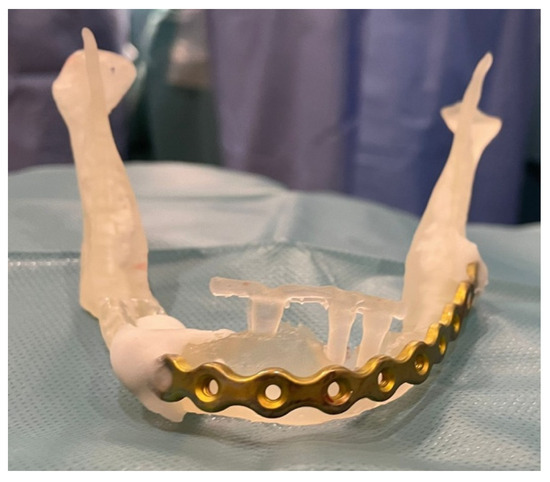

3.1. Case 1

3.2. Case 2